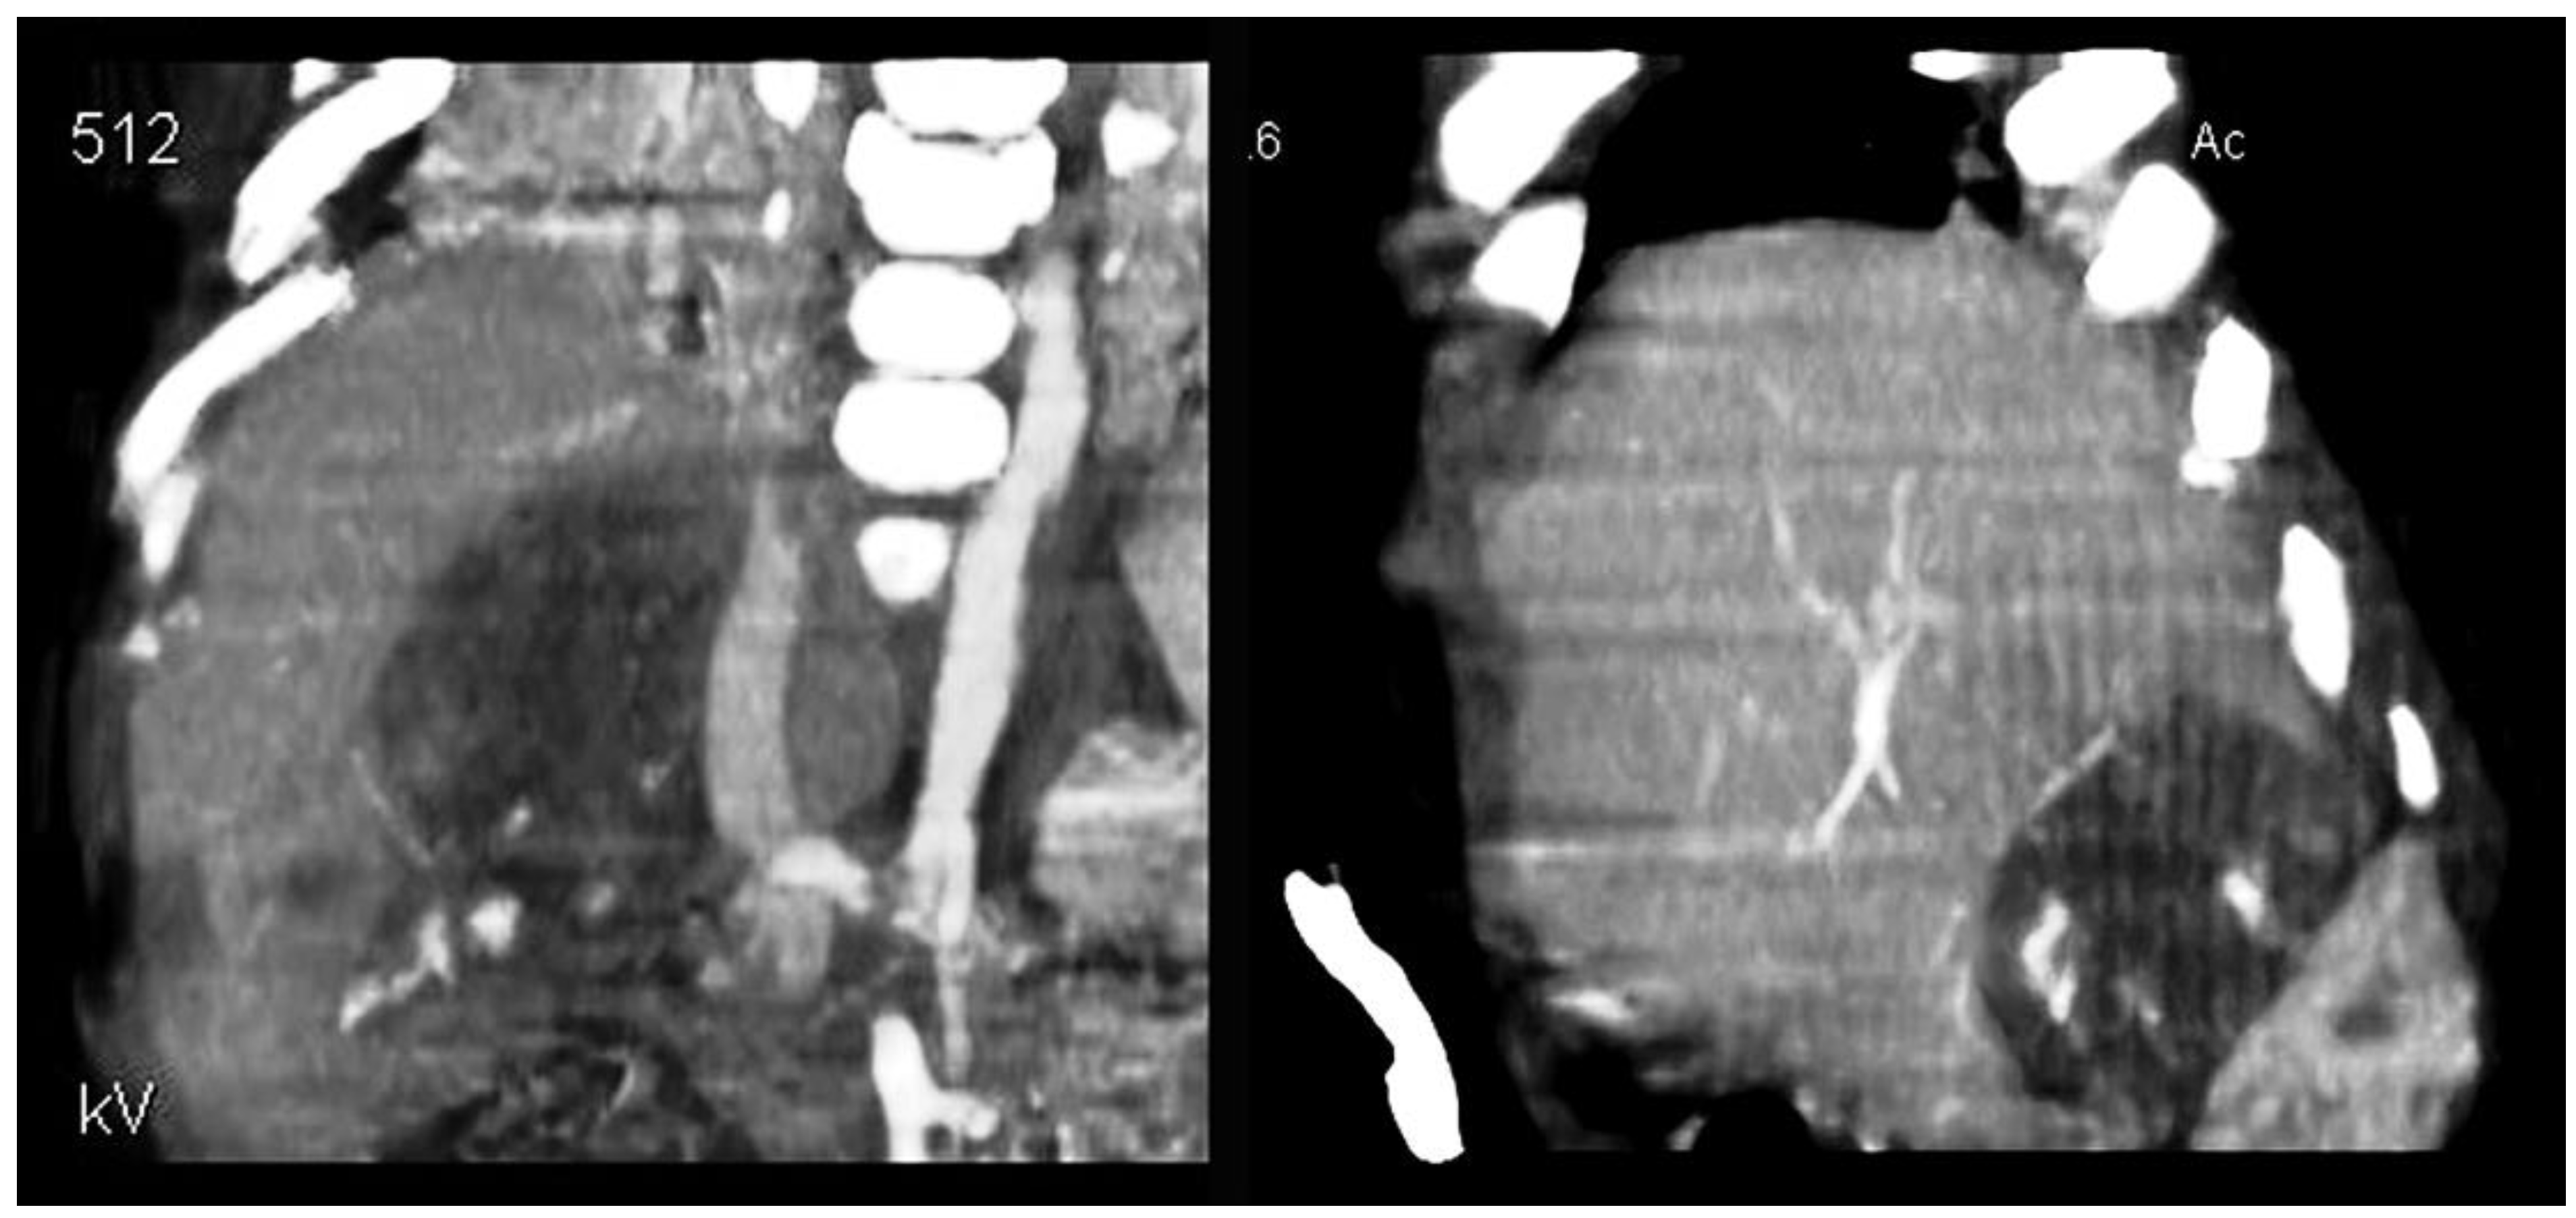

The case was discussed within our multidisciplinary team dealing with pediatric oncology. In agreement with our colleagues in oncology and in accordance with the SIOPEL protocol, we decided to start neoadjuvant chemotherapy with four subsequent cycles of cisplatin (70 mg/m2/day). At the end of the pharmacological treatment, a reduction in AFP and total bilirubin in the blood was observed. A new total-body computerized tomography (CT) showed a marked reduction in the mass (Figure 1) and confirmed the absence of systemic metastases.

Figure 1. Legend—CT scan: marked reduction in the liver mass (image on the left before treatment) after chemotherapy (image on the right).